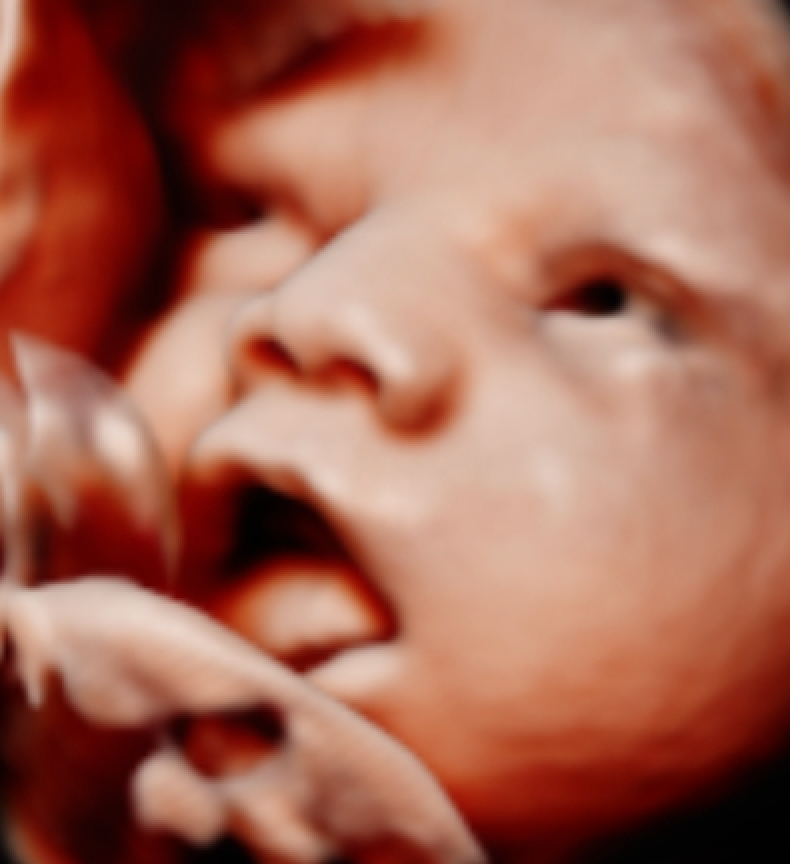

Browsing our 4D ultrasound photos gives you a clear idea of what your session can look like. You will see a range of images, from early 2D visits and gender reveal moments to rich 3D, 4D, and HD live facial detail captured during the most popular weeks between 26 and 32 weeks. Babies are unpredictable, but we have spent many sessions helping families get those sweet expressions, tiny stretched arms, and peaceful faces that you will want to hold onto for years.

Our experienced team guides you through every part of the visit. When baby needs encouragement to move into a better position, we walk you through simple techniques that can help. We never rush through the session looking for a quick shot. We take time, adjust angles, and work patiently to find those moments that matter most.

Hydration is one of the most helpful things you can do before your visit. Staying well hydrated in the days leading up to your appointment supports clearer amniotic fluid, which directly affects image quality. Drink plenty of water starting several days before you come in.